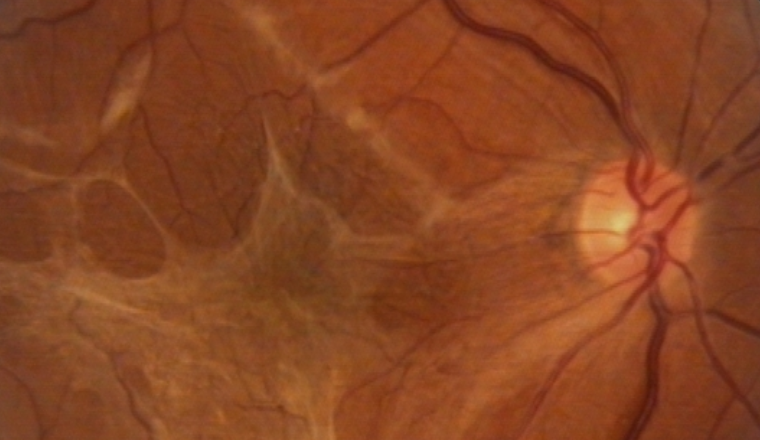

黄斑前膜(macular epiretinal membrane)──手術を勧めるタイミングとは?

Q: 黄斑前膜(macular epiretinal membrane)があり、OCT(光干渉断層計)で“5ラインズ”撮影した時には網膜の浮腫または肥厚が明らかですが、変視症はわずかで矯正視力の低下もありません。この患者 … 続きを読む 黄斑前膜(macular epiretinal membrane)──手術を勧めるタイミングとは?